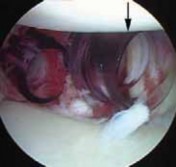

The surgical approach begins with the establishment of a standard posterior viewing portal, placed approximately 2 cm inferior and 1 cm medial to the posterolateral corner of the acromion. Upon entering the joint, a meticulous diagnostic sweep is performed. The surgeon must systematically evaluate the biceps anchor, the superior labrum, the articular surfaces of the humerus and glenoid, the rotator cuff footprint, and the entire capsulolabral complex. Particular attention is directed to the anteroinferior quadrant to confirm the presence of a Bankart or ALPSA lesion. The size and depth of any Hill-Sachs lesion are evaluated dynamically by taking the arm through a range of motion to assess for "engagement" over the anterior glenoid track.

Following the diagnostic sweep, two anterior working portals are established using an outside-in spinal needle localization technique. The anterosuperior portal is typically placed just anterior to the acromioclavicular joint, entering the joint through the rotator interval superior to the biceps tendon; this serves primarily for fluid management and suture retrieval. The critical anteroinferior working portal is placed just superior to the upper border of the subscapularis tendon, ensuring an optimal trajectory (approximately 45 degrees to the glenoid face) for anchor insertion along the anteroinferior glenoid rim. A clear cannula (typically 5.5 mm or 8.25 mm) is introduced to facilitate smooth instrument passage and suture management.

The foundation of a successful arthroscopic stabilization is the meticulous mobilization of the capsulolabral complex. In chronic cases, the torn labrum and IGHL frequently heal in a medially displaced position along the anterior glenoid neck (the ALPSA lesion). Using a combination of arthroscopic elevators, rasps, and electrocautery, the surgeon must aggressively liberate this tissue from the scapular neck. The release must extend inferiorly to the 6 o'clock position to adequately mobilize the inferior capsule. Once the tissue is freed and can be easily reduced to the articular margin, the anterior glenoid neck is lightly decorticated using a motorized burr or rasp. This critical step removes fibrous tissue and exposes bleeding cancellous bone, creating an optimal biological environment for robust soft-tissue healing.